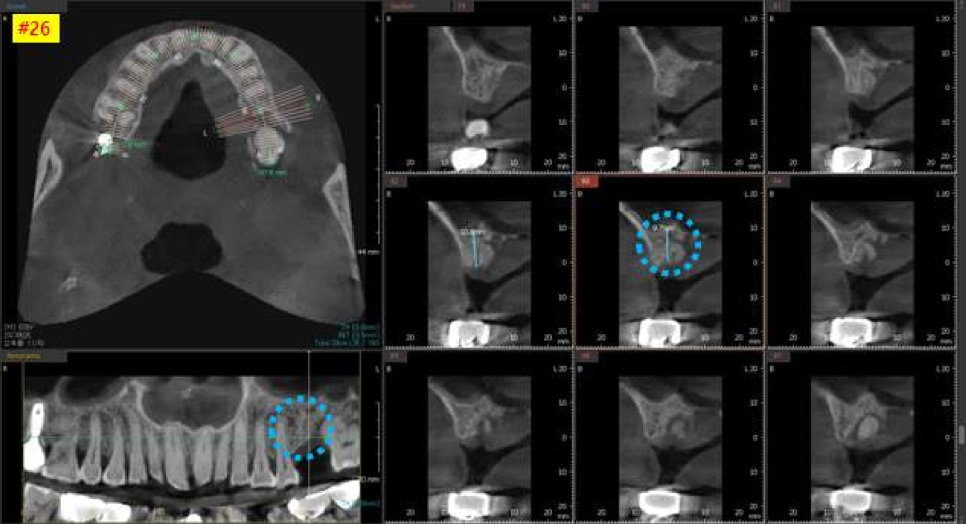

수술 전, 3차원 CT 촬영을 통하여

더욱 정밀하게 수술 계획을 세웁니다.

가장 안전하고 좋은 위치에

임플란트를 안전하게 심기 위한 작업입니다.

왼쪽 위 큰어금니 CT 사진을 보시면

비교적 뼈가 하얗게 잘 차있는 모습을 볼 수 있습니다.

인접치 관계를 고려해서

가장 이상적이고 안전한 위치를 찾아

적정한 두께와 길이의 임플란트를 선택합니다.